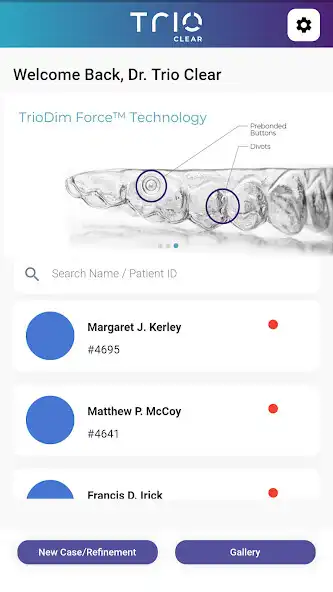

B. DOCTOR INTERFACE

Easily manage all the patient cases with the TrioClearTM Aligner Mobile App, saving you effort and chair time.

Reminder: This interface of this App is intended for TrioClearTM providers only.

DOCTOR INTERFACE - FEATURES:

- Capture and save required photos on the App for case submissions later on the TrioClearTM Doctor Submission Portal.

- View all the patient profiles, photo records and treatment status.

- View & approve treatment plans.

- Receive case log updates.

- Keep track of treatment progress with photos and aligner wear time stats submitted by patients at different stages if necessary.